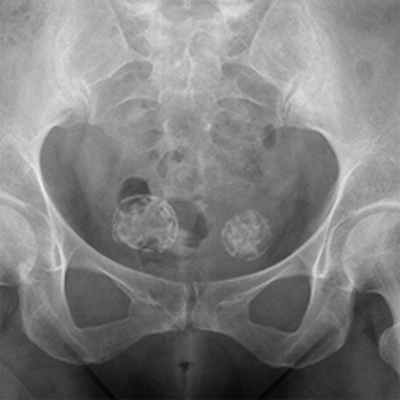

• Рентгенография обычно позволяет выявить литическое образование. Некоторые опухоли молочной и предстательной желёз на рентгенограммах представлены бластическими образованиями •• Остеолиз визуализируется рентгенологически при разрушении 40–50% костной ткани и достижении размеров более 1 см, сопровождается гиперкальциемией и экскрецией содержащих гидроксипролин пептидов •• Остеобластические повреждения выявляют при радионуклидном сканировании костей и рентгенологическом исследовании (увеличение плотности кости и склероз). Остеобластические повреждения могут сочетаться с увеличением в сыворотке крови концентрации ЩФ и гипокальциемией.

Рак простаты чаще бывает бластным, рак легкого – литическим, а рак молочной железы может быть бластным или литическим.

- Деструкция с «разъеданием» костной структуры на рентгенограммах выглядит как дефект – «дырка», такой вариант метастазирования называют остеолитическим, что буквально означает «съеденная кость».

- При утолщении кости за счёт опухоли рентгенограмма выявляет «плюс ткань», тогда говорят об остеопластическом метастазировании.